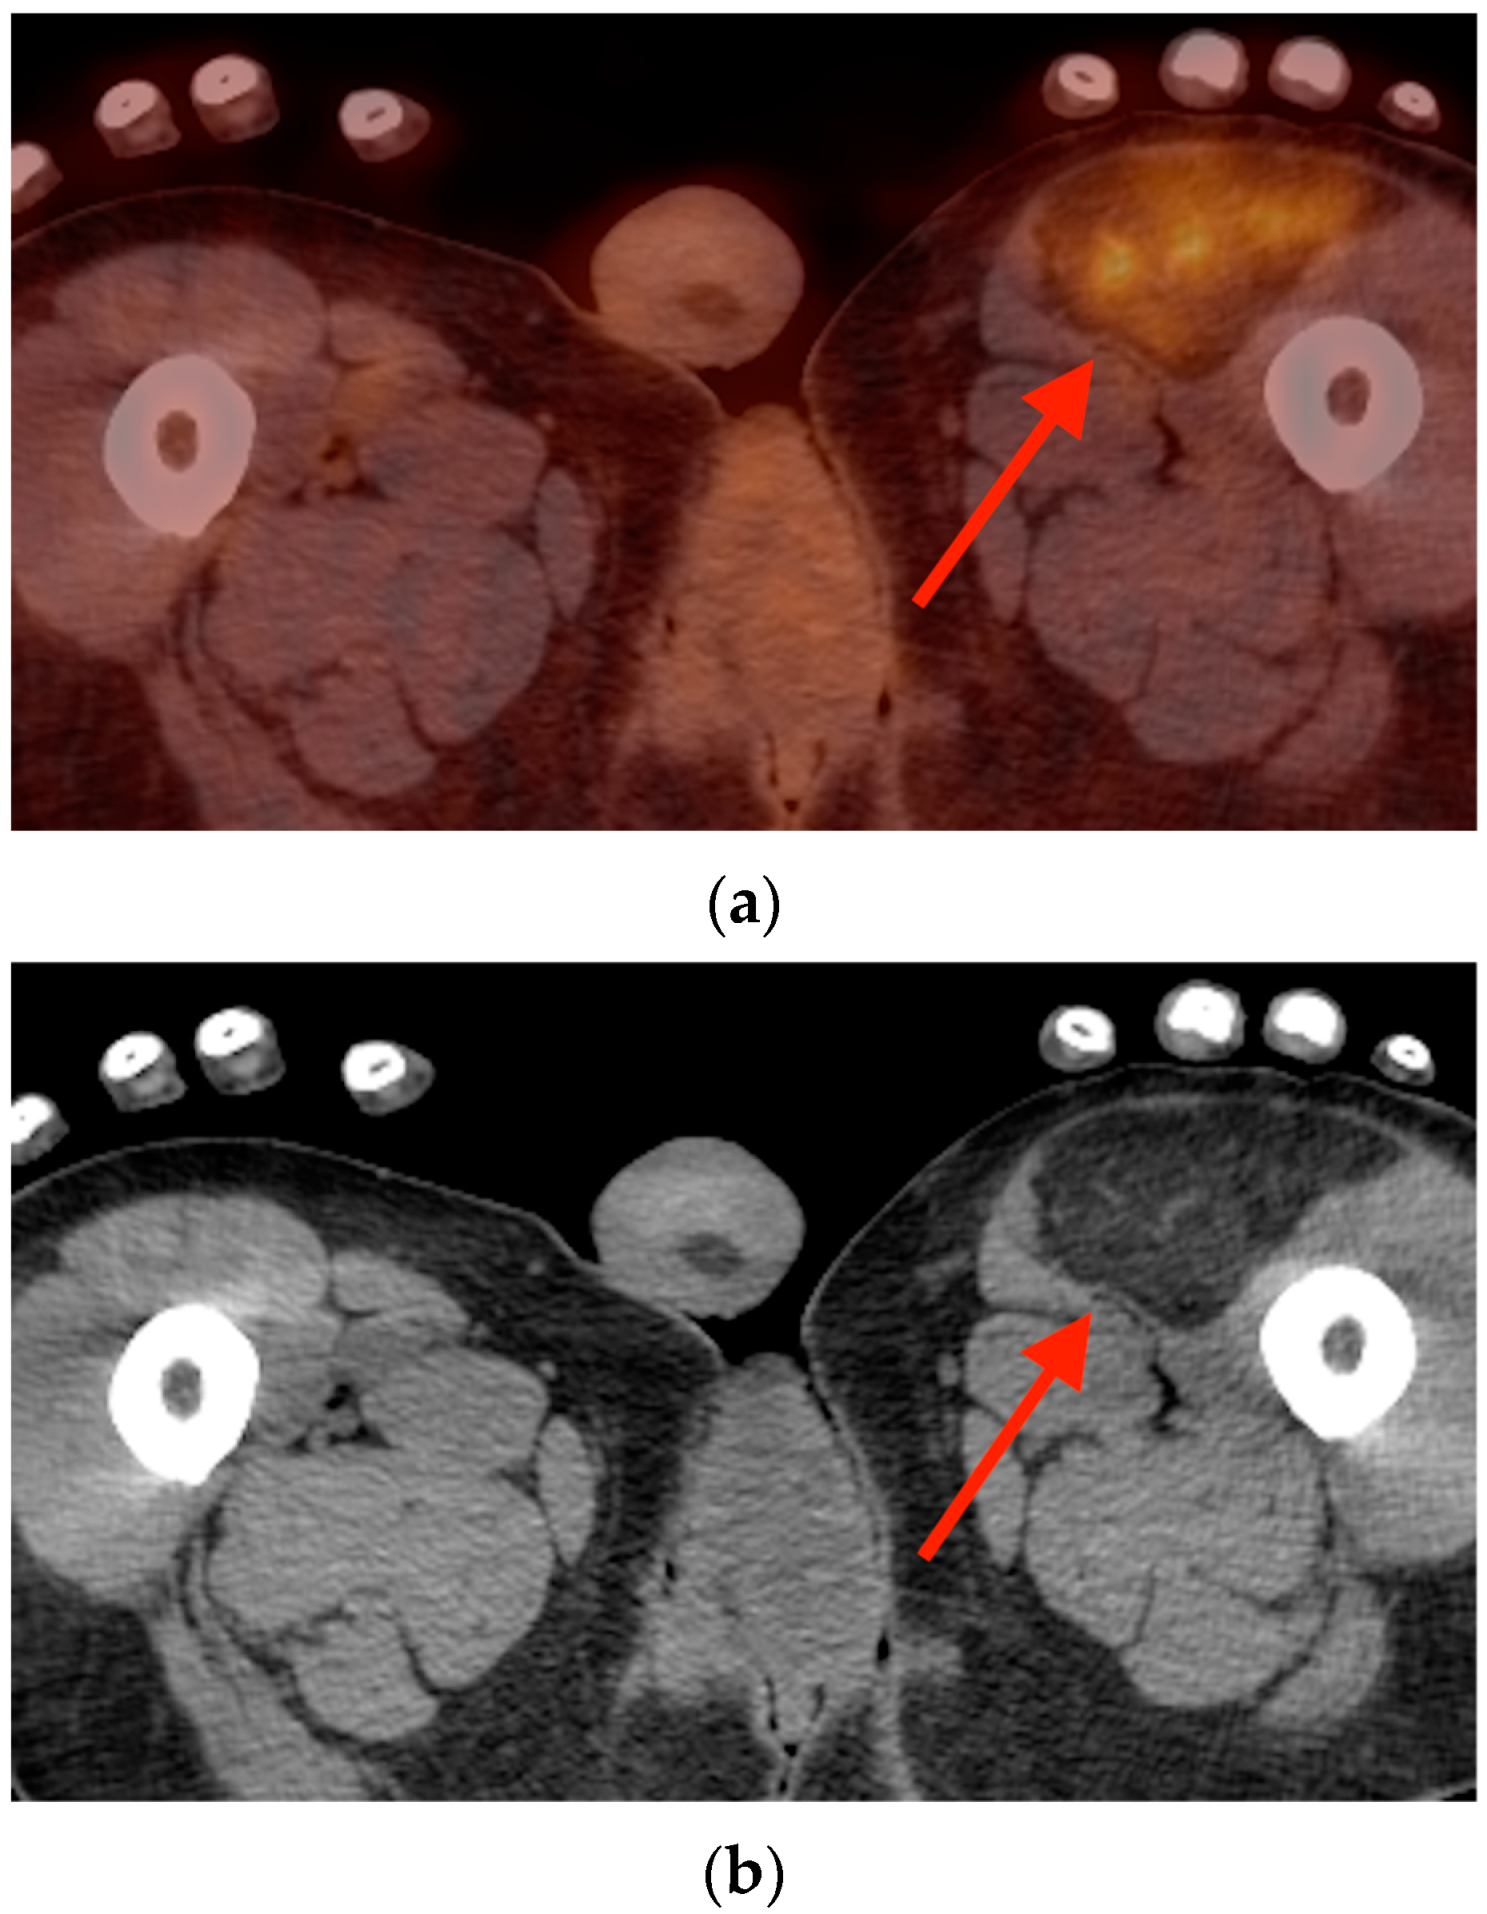

5.3. Hibernoma

- Mavrogenis, A.F.; Coll-Mesa, L.; Drago, G.; Gambarotti, M.; Ruggieri, P. Hibernomas: Clinicopathological features, diagnosis, and treatment of 17 cases. Orthopedics 2011, 34, e755–e759. [Google Scholar] [CrossRef]

- Smith, C.S.; Teruya-Feldstein, J.; Caravelli, J.F.; Yeung, H.W. False-positive findings on 18F-FDG PET/CT: Differentiation of hibernoma and malignant fatty tumor on the basis of fluctuating standardized uptake values. AJR Am. J. Roentgenol. 2008, 190, 1091–1096. [Google Scholar] [CrossRef]

- Baffour, F.I.; Wenger, D.E.; Broski, S.M. 18F-FDG PET/CT imaging features of lipomatous tumors. Am. J. Nucl. Med. Mol. Imaging 2020, 10, 74–82. [Google Scholar] [PubMed]

- Al Hmada, Y.; Schaefer, I.M.; Fletcher, C.D.M. Hibernoma Mimicking Atypical Lipomatous Tumor: 64 Cases of a Morphologically Distinct Subset. Am. J. Surg. Pathol. 2018, 42, 951–957. [Google Scholar] [CrossRef] [PubMed]